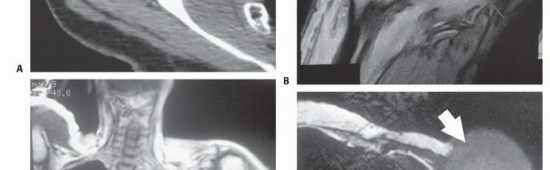

لفهم جراحة استئصال أورام الكتف مع الحفاظ على الطرف، من الضروري أولاً فهم التشريح المعقد لهذه المنطقة. حزام الكتف ليس مجرد مفصل واحد، بل هو منظومة معقدة من العظام، المفاصل، العضلات، الأربطة، الأوتار، الأعصاب، والأوعية الدموية التي تعمل بتناغم لتمكين الذراع من الحركة في جميع الاتجاهات. هذا التعقيد هو ما يجعل جراحة الأورام في هذه المنطقة تحديًا كبيرًا، ويتطلب جراحًا ذا خبرة استثنائية مثل الأستاذ الدكتور محمد هطيف.

* الضفيرة العضدية (Brachial Plexus): شبكة معقدة من الأعصاب التي تنشأ من الرقبة وتمر عبر الإبط، وتغذي جميع عضلات الذراع واليد وتوفر الإحساس. أي إصابة بها يمكن أن تؤدي إلى فقدان كبير للوظيفة.

* الشريان تحت الترقوة والوريد تحت الترقوة: الأوعية الدموية الرئيسية التي تزود الذراع بالدم وتصرفه.